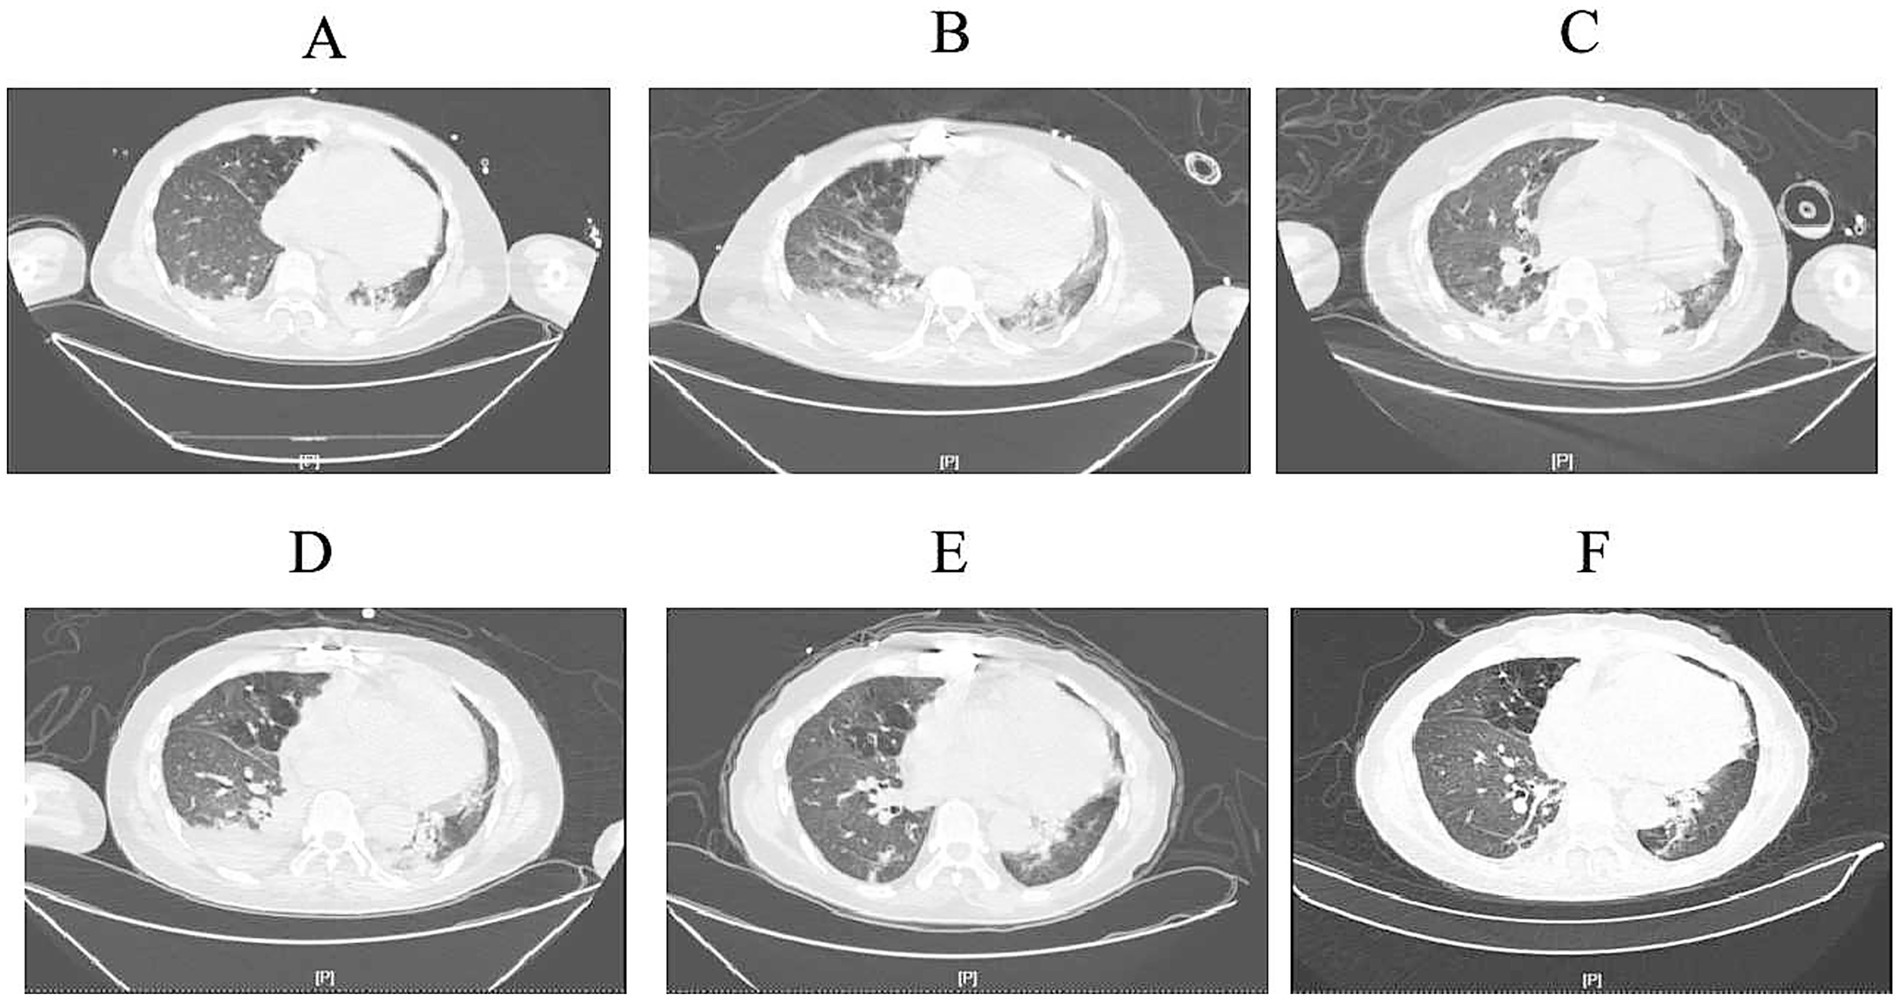

By March 29th, the patient’s exhibited worsening infection markers and a thrombus at the ECMO site in the right lower limb, leading to ECMO removal. L-AMB dosage was adjusted to 5 mg/kg daily after clinical pharmacy consultation. Chest CT revealed bilateral pulmonary inflammation, atelectasis, and minimal pleural effusion (Figure 1A).

Figure 1. Computed tomography images. (A) (March 30th): Initial imaging showed scattered inflammatory infiltrates in both lungs, partial atelectasis of the lower lobes, and minimal bilateral pleural effusion. (B) (April 7th): Progressive inflammatory changes with scattered nodules in both lungs, slight worsening of inflammation, persistent pleural effusion, and increased right-sided effusion volume. (C) (April 17th): Stable inflammatory changes in both lungs, persistent lower lobe atelectasis, and reduced right-sided pleural effusion. (D) (April 22nd): Imaging consistent with prior findings, showing persistent inflammatory changes, pleural effusion, and partial atelectasis. Right-sided effusion volume increased. (E) (May 6th): Gradual resolution of inflammation, improvement in lower lobe atelectasis, and reduced pleural effusion volume. (F) (May 10th): Ongoing resolution of inflammatory changes, partial atelectasis, and minimal right-sided pleural effusion with slight volume increase compared to prior scan.

On April 7th, the patient’s condition slightly deteriorated, with chest CT showing increased inflammatory changes (Figure 1B). Bronchoalveolar lavage fluid NGS results showed Pseudomonas aeruginosa and viral pathogens, prompting the addition of polymyxin B nebulization and ganciclovir for mucormycosis.

On April 17th, the patient’s expectorated sputum cultures showed CRPA. A chest CT showed scattered inflammatory changes in both lungs (Figure 1C). Despite treatment with polymyxin B, the sputum cultures still showed CRPA, and there was no significant improvement on the chest CT. Considering the poor efficacy of polymyxin B and the absence of Rhizopus arrhizus in the last two NGS results, polymyxin B (intravenous), amphotericin B cholesterol sulfate complex nebulization were discontinued. Instead, the patient was given ceftazidime-avibactam (2.5 g/8 h by intravenous drip), polymyxin B nebulization and oral isavuconazole.

By April 20th, the patient developed leukopenia, attributed to ganciclovir, which was subsequently discontinued. On April 22nd (Figure 1D), the patient’s condition improved with reduced Pseudomonas aeruginosa sequences on NGS, confirming the efficacy of the current regimen. Antimicrobial de-escalation was performed on May 6th (Figure 1E), transitioning to piperacillin-tazobactam (4.5 g/12 h) based on clinical improvement and infection marker trends. A follow-up chest CT on May 10th demonstrated further resolution of inflammation (Figure 1F), and the patient was discharged on oral isavuconazole.